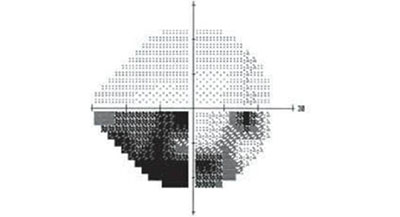

眼睛患上青光眼會同時出現(xiàn)兩個特征:視神經(jīng)萎縮,視野缺損

視野決定了眼睛能看到的范圍,如果視野出現(xiàn)缺損(上圖黑色部分),就說明眼睛在黑色部分里是看不見的。